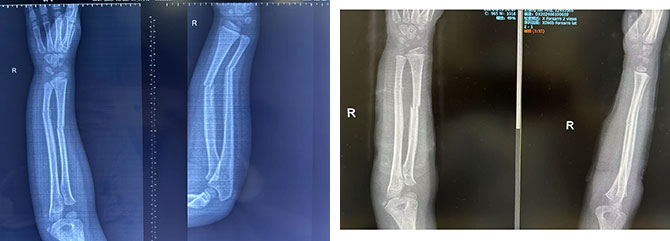

患者2:男,6岁,右侧桡尺骨双骨折,复位前后对比

复位前 复位后